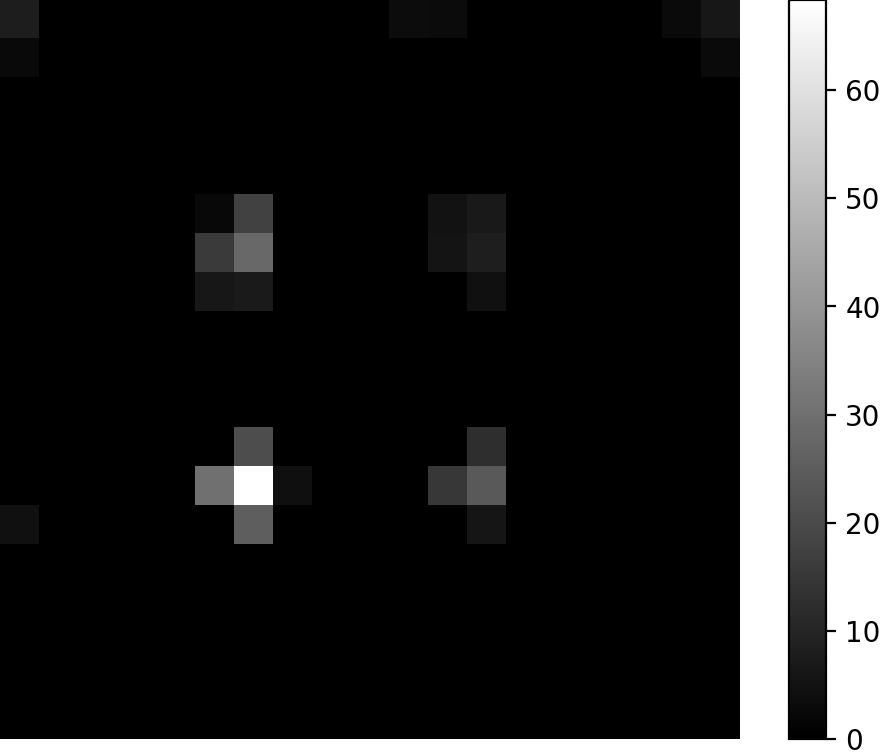

Fig. 1: Selected slices for the Tikhonov reconstruction, the DIP with the αisubscript𝛼𝑖\alpha_{i} with the highest PSNR levels and the PnP (cf. Tab. 2). For the shape phantom we display the 10-th xz-slice, for the resolution phantom the 10-th xy-slice and for the concentration phantom the 13-th xy-slice.

Selected slices of the reconstructions are displayed in Fig. 1, we refer the interested reader to the supplementary material (Section S6) for a full display of all slices of the reconstructions.

An overview of the results obtained in terms of PSNRmaxsubscriptPSNRmax\mathrm{PSNR}_{\mathrm{max}} and SSIMmaxsubscriptSSIMmax\mathrm{SSIM}_{\mathrm{max}} are displayed in Tab. 2. The 1superscript1\ell^{1}-PnP method obtains higher SSIM for all phantoms whereas the PSNR score of the 1superscript1\ell^{1}-PnP is significantly higher for the shape phantom, higher for the resolution phantom and lower but comparable for the concentration phantom.

Because the 19×19×1919191919\times 19\times 19 resolution of the reconstructions, the visual quality assessment of the differences between reconstructions can be difficult. For a better understanding of the differences we have plotted in Fig. 2 a 1D line plot that compares the graph of the reconstructions and the reference CAD model. In Fig. 2 we can see that the Tikhonov method smooths out the reference and takes negative values, whereas the the DIP tends to overshoot when compared to the PnP reconstruction. It is worth noting that the DIP can present artifacts in the reconstruction (cf. Fig. 1(h)).